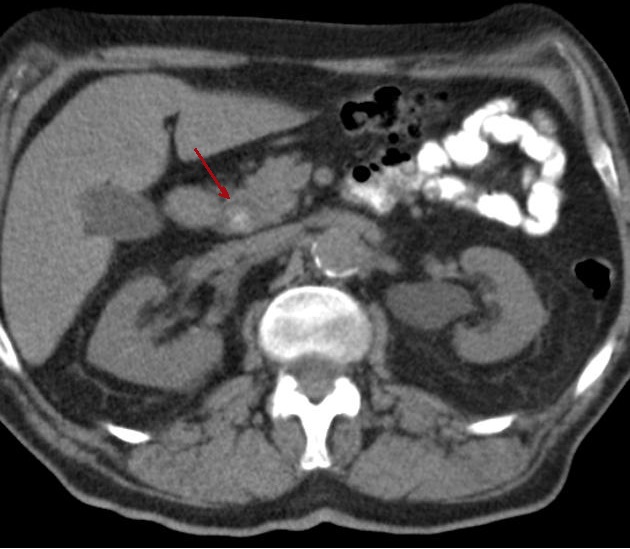

Aspect radiologique d'une

calcul choledocienne .Image de cible du calcul avec

central hyperdensite et a contour de faible de

densite . Image TDM en coupe axiale |

|

Aspect de cible d'une calcul

choledocienne ( fleche rouge ) . Portion dilate en

amont du canal choledoque peut envoyant bien sur ce

coupe . |